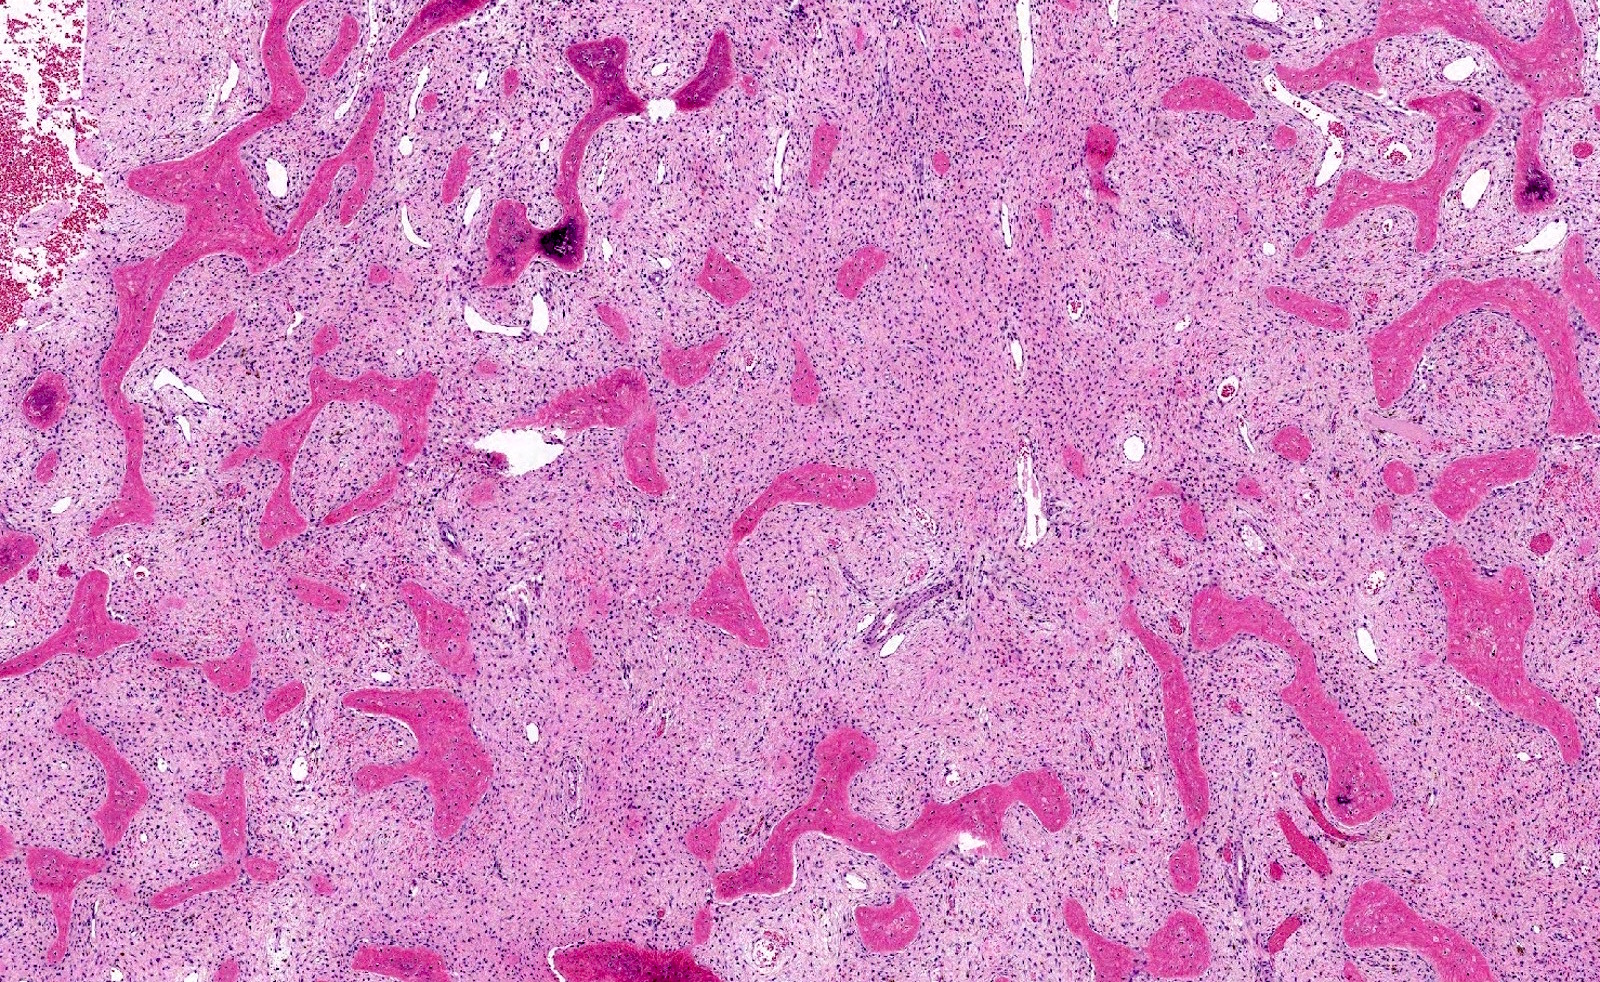

Microscopic (histologic) description

- Branching and anastomosing irregular trabeculae of woven bone ("C" and "S" shapes) with no conspicuous osteoblastic rimming

- No / rare osteoclasts

- Intervening fibrous stroma containing cytologically bland spindle cells, without prominent cytologic atypia

- Secondary aneurysmal bone cyst-like changes may also be seen (Turk Patoloji Derg 2018;34:234)

Microscopic (histologic) images